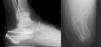

Postoperative CT (defined as that performed prior to hospital discharge of the patient or in the first month of follow-up) was performed only in those cases in which the surgeon considered that pain radiology would not clarify the quality of the joint reduction, resulting in a total of 17 cases (37% of the series, six Sanders type IV patients treated with the “L” approach, nine Sanders type III patients treated by sinus tarsi and two Sanders type II patients treated with closed reduction and fixation with screws). The reduction of the posterior subtalar joint measured by CT was satisfactory in 12 cases (defined as an articular displacement < 2 mm). In the other five cases the displacement was above 2 mm (one Sanders type iv case, one Sanders type iii case of tarsi sinus, one Sanders type iii case with indirect reduction and cannulated screws and two Sanders type ii cases also with indirect reduction). Reintervention was decided in only one case (patient with Sanders type II fracture) with an “L” approach and low-profile plate, with good radiological and functional outcome. Of the remaining four cases the risk/benefit balance of further surgery called for conservative treatment, particularly due to the further aggression to soft tissues. The average preoperative Böhler angle was 6.45 ± 10.21 ([-22]-25) and postoperative angle was 20.46 ± 7.09 (4−38). CT in follow-up (defined as over one year after surgery) was performed in 31 cases, only in those where three was suspicion of a post-traumatic degenerative pathology following analysis of plain radiology: subtalar osteoarthritis was diagnosed in 19 cases (symptomatic in 12, seven of them treated with subtalar arthrodesis) and calcaneo-cuboid osteoarthritis in six cases (only one symptomatic and treated conservatively) (Table 3). The AOFAS was 74.28 ± 18.98 (27−100) and the VAS 4.14 ± 2.98 (2–9).

The results of this study indicate that postoperative CT is the most reliable imaging technique for verifying accurate anatomical reduction in surgically treated calcaneal joint fractures. We carried out a literature search on the indication of this test in treatment protocol and for this we used the PubMed search engine dated August 2019 with the following key words: calcaneal fractures and treatment, and CT scan, in the last five years. Our aim was to assess the published works on surgically treated calcaneal fractures for which postoperative CT was conducted (Fig. 4). A total of 652 results was obtained. After the elimination of non-related articles and articles published more than five years previously, a total of 117 articles met with our search criteria, of which only 29 requested postoperative CT (Fig. 4). Of these, only two reported on the indication of postoperative CT request,13,14 and in the remaining 27 the cause of the indication for this test was not specified and it was inferred that this simply formed part of their protocol, as occurs in other centres for the assessment of joint fractures before and after surgery. In 2017 De Muinck-Keizer et al.13 conducted a study for the assessment of joint reduction and the correct positioning of osteosynthesis material in calcaneal fractures, highlighting in their article the absence of postoperative protocols based on carrying out postoperative CT; the authors concluded, following the design of a specific point system, that the CT provided extremely valuable information on their two initial aims. Also in 2019, Beerekamp et al.14 carried out an interesting comparative study of different imaging techniques: intraoperative 2D and 3D fluoroscopy for assessment of joint reduction and the positioning of implants, concluding that although 3D intraoperative fluoroscopy is very useful, particularly in the assessment of the positioning of implants, CT remained the study of choice. To sum up, our review of the literature demonstrated that postoperative outcomes are not systematically analysed with postoperative CT or in patient follow-up and it its use is the only way to demonstrate anatomical reduction (displacement under 2 mm) and the correct positioning of implants.